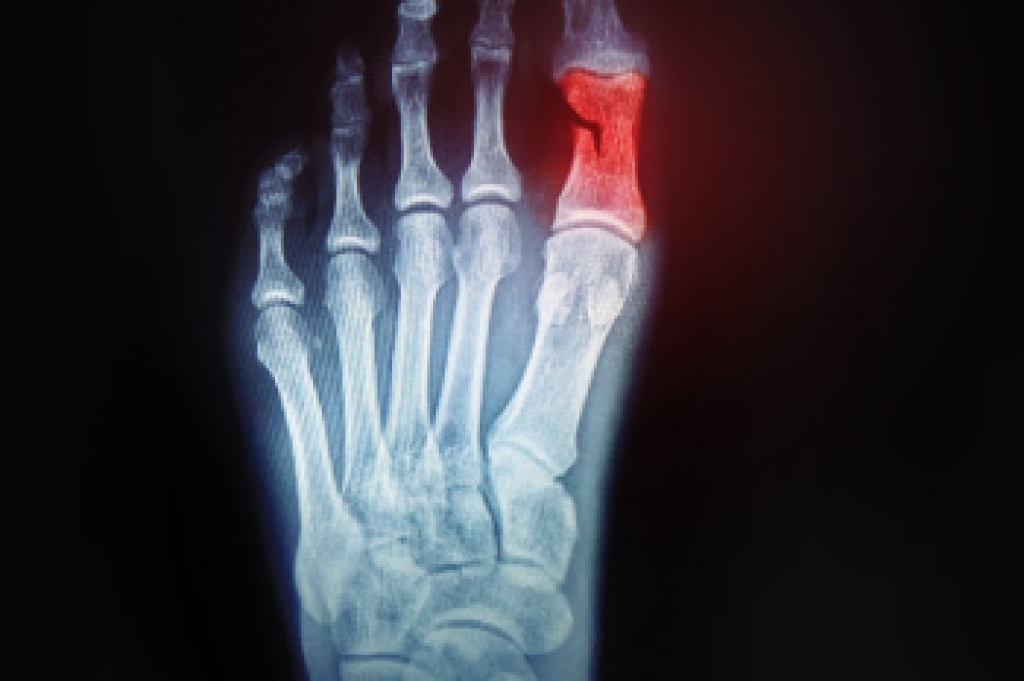

Broken toes can cause significant discomfort and limit mobility. Toe fractures usually occur from stubbing the toe, dropping something heavy on the foot, or sustaining a sports-related impact. Symptoms include swelling, bruising, and pain when walking or applying pressure. Diagnosis is confirmed through an exam and imaging to assess the extent of the fracture and determine if the bone is displaced. Stable, nondisplaced fractures may be managed with protective footwear to reduce movement and pressure, while displaced fractures often require a procedure to realign the bone. Fractures of the big toe tend to be more serious due to this toe’s role in balance and walking. Big toe injuries may require stabilization or even surgery if the damage is severe. A podiatrist can provide a proper diagnosis, realignment, and supportive devices to promote healing and prevent long-term complications. If you are experiencing pain from a broken toe, it is suggested that you make an appointment with a podiatrist for an exam, diagnosis, and treatment.

Although most people try to avoid foot trauma such as banging, stubbing, or dropping heavy objects on their feet, the unfortunate fact is that it is a common occurrence. Given the fact that toes are positioned in front of the feet, they typically sustain the brunt of such trauma. When trauma occurs to a toe, the result can be a painful break (fracture).

Severe toe fractures may be treated with a splint, cast, and in some cases, minor surgery. Due to its position and the pressure it endures with daily activity, future complications can occur if the big toe is not properly treated.